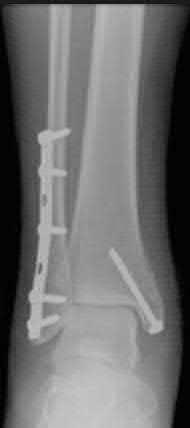

A 64-year-old woman is thrown off a horse, sustaining the injury shown in Figures A and B. She undergoes surgical fixation as seen in Figures C through E. What is the most commonly reported complication of this procedure?

The patient in the scenario has a 2-part proximal humerus fracture treated with a locking plate as seen in Figures A-E. The most common complication with the use of this implant is screw penetration. The terms screw cut out and penetration are often used interchangeably in the literature with cut out appearing more frequently in reports regarding intertrochanteric fractures.

Owsley et al retrospectively reviewed 53 proximal humerus fractures treated with locking plates and the same post-operative protocol. The most common complication was screw cut out or penetration, followed by varus displacement. They concluded that 3 and 4-part fractures in patients over 60 years have a higher incidence of failure.

Agudelo et al retrospectively reviewed 153 patients at a level-one trauma center treated with proximal humerus locking plates, investigating modes of failure for the implant. They determined that varus malreduction (head-shaft angle